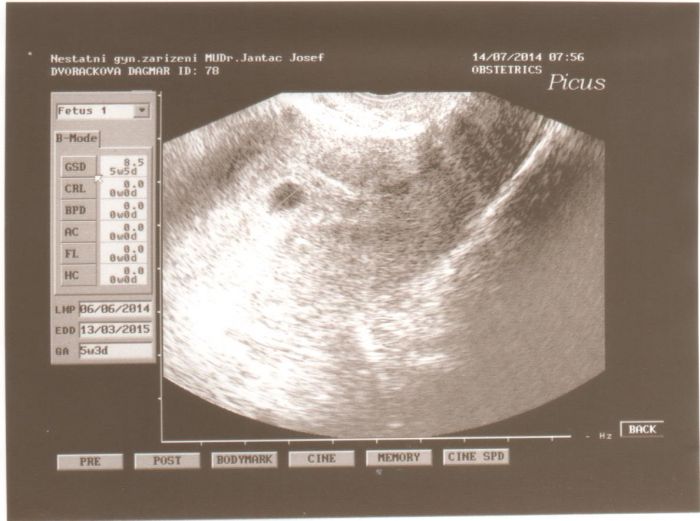

Ahoj holky, tak mám 1. kontrolu a lékařské potvrzení těhotenství za sebou. Zatím se zdá vše ok, ale musím být v klidu doma. Mám problémy se srdíčkem, tak aby bylo vše v klidu a ok. Toto je náš mimísek.

gloxini, pekna fotecka, tak odpocivej at se pekne vyviji